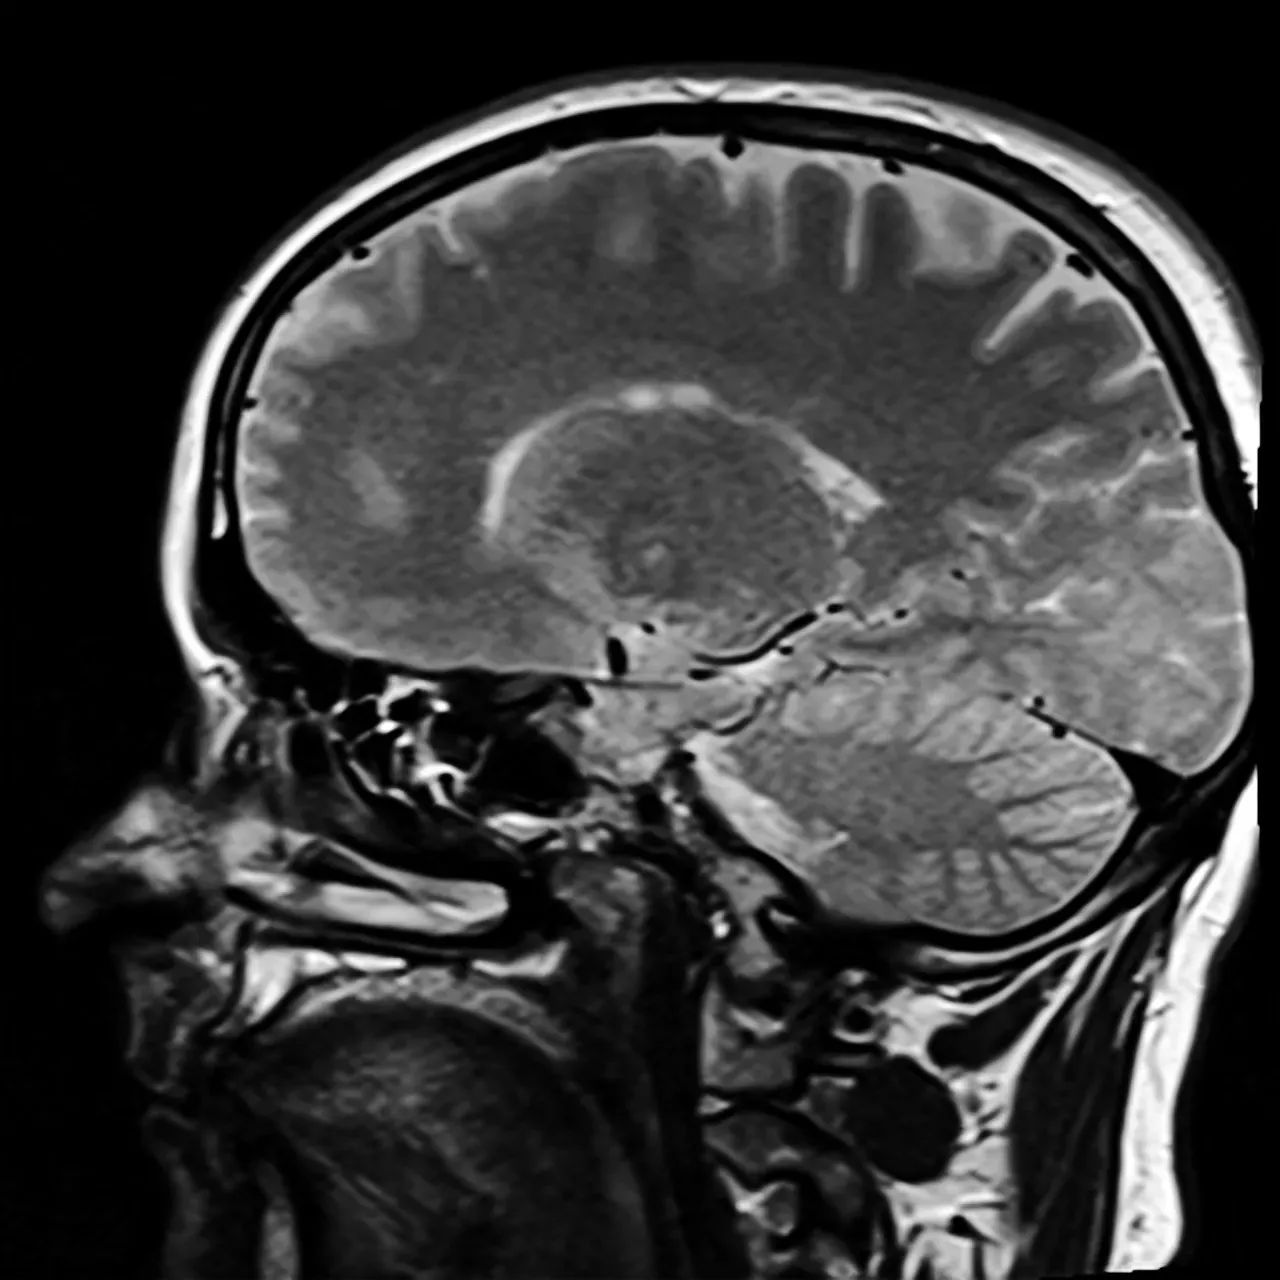

Featured Image. Credit CC BY-SA 3.0, via Wikimedia Commons

Functional magnetic resonance imaging has transformed how we study the living brain. BOLD fMRI depicts changes in deoxyhemoglobin concentration consequent to neural metabolism, and since its inception in 1990, has been widely employed in thousands of studies of cognition and clinical applications. Researchers can now watch specific brain regions light up when you remember your childhood home or move your hand to pick up a coffee cup.

Scans taken while subjects engage in tasks enable researchers to link neural structure activity with particular functions, experiences, or behaviors. We can identify the neural patterns underlying fear, hunger, even complex social emotions. It’s not magic, though sometimes it feels close. Still, something critical gets lost in the translation from brain scan to lived experience.